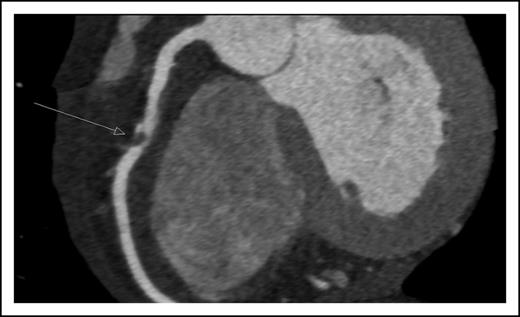

A 45-year-old man presented with new onset of chest pain and anemia. Cardiac computerized tomography revealed normal systolic function, but with significant narrowing of the right coronary artery (Figure 1). Acute coronary syndrome (ACS) was diagnosed. The white blood count was 10 × 109/L with 20% blasts. BM aspiration and biopsy were diagnostic for AML, molecularly characterized with normal cytogenetics and NPM1, as the only identified mutation.

Coronary computerized tomography demonstrating atherosclerotic occlusion of the right coronary artery.